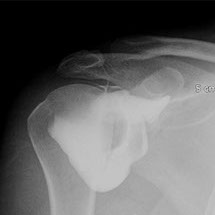

Cet examen consiste à injecter à l’aide d’une aiguille, sous guidage radiologique un produit de contraste iodé à l’intérieur d’une articulation. Les articulations concernées sont variées : genou, cheville, épaule, coude, poignet, hanche.

L’arthrographie est généralement immédiatement complétée par un scanner de l’articulation (arthroscanner). Ceci ne nécessitera pas de deuxième piqûre.

L’arthrographie, généralement couplée à l’arthroscanner permet au radiologue d’établir un diagnostic précis sur l’état des cartilages de l’articulation concernée, de déceler des ruptures partielles ou complètes des tendons, des ligaments, ou encore de déceler des corps étrangers au sein des articulations explorées. Cette exploration peut être couplée à une infiltration dans le même temps opératoire.